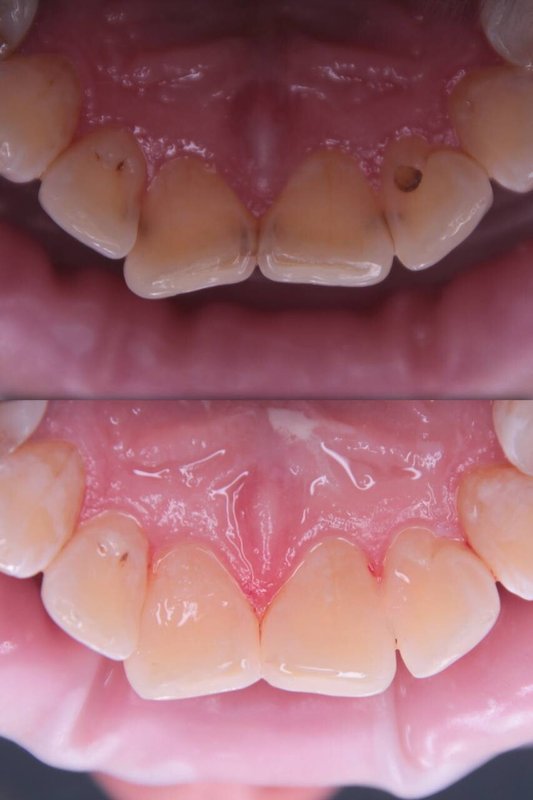

Фотогалерея

Проводит диагностику заболеваний зубов и полости рта используя в работе искусственный интеллект, компьютерную томографию, 3D-сканирование, операционный микроскоп.

Занимается эстетической реабилитацией улыбки путем отбеливания, художественной реставрацией и виниров, а также лечением таких заболеваний, как кариес, пульпит, периодонтит, гингивит, гиперестезия, флюороз и др.